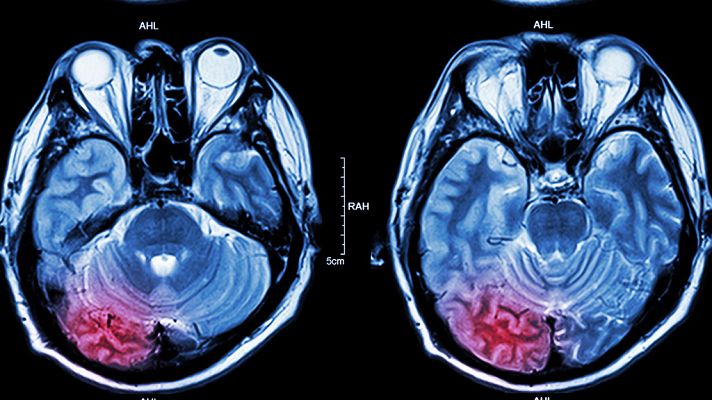

El ictus es la segunda causa de muerte en España. Y aunque se asocia a la tercera edad, cada vez más afecta a gente más joven. En los últimos diez años, el número de pacientes de ictus de entre 25 y 44 años se ha incrementado un 43%. Un hecho que tiene que ver con los hábitos de vida.